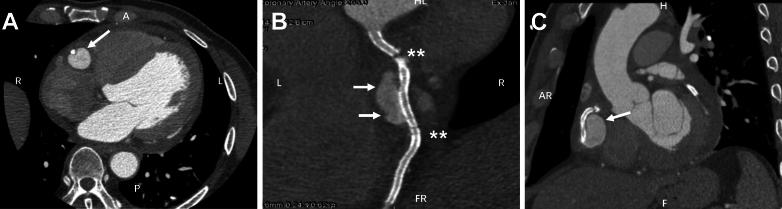

Formation of a coronary artery aneurysm (CAA), especially a giant CAA, after percutaneous coronary intervention for chronic total occlusion (CTO) is a rare complication. Therapeutic approaches include surgical procedure, covered stent, and medical treatment. Here, we report a 47-year-old man readmitted due to chest distress who had undergone right coronary artery CTO recanalization 6 months earlier. Diagnostic coronary artery angiography revealed a giant aneurysm at the stented middle segment of the right coronary artery; it was >20 mm in diameter. This is the first report on a secondary giant CAA after CTO recanalization that was subsequently excluded with deployment of a covered stent.

经皮冠状动脉介入治疗慢性完全闭塞病变(CTO)后形成冠状动脉瘤(CAA),尤其是巨大冠状动脉瘤,是一种罕见的并发症。治疗方法包括外科手术、覆膜支架置入和药物治疗。在此,我们报告一例47岁男性患者,因胸部不适再次入院,该患者6个月前接受了右冠状动脉CTO再通术。诊断性冠状动脉造影显示右冠状动脉支架置入的中段有一个巨大动脉瘤,直径>20mm。这是首例关于CTO再通术后继发性巨大冠状动脉瘤并随后通过覆膜支架置入得以排除的报告。